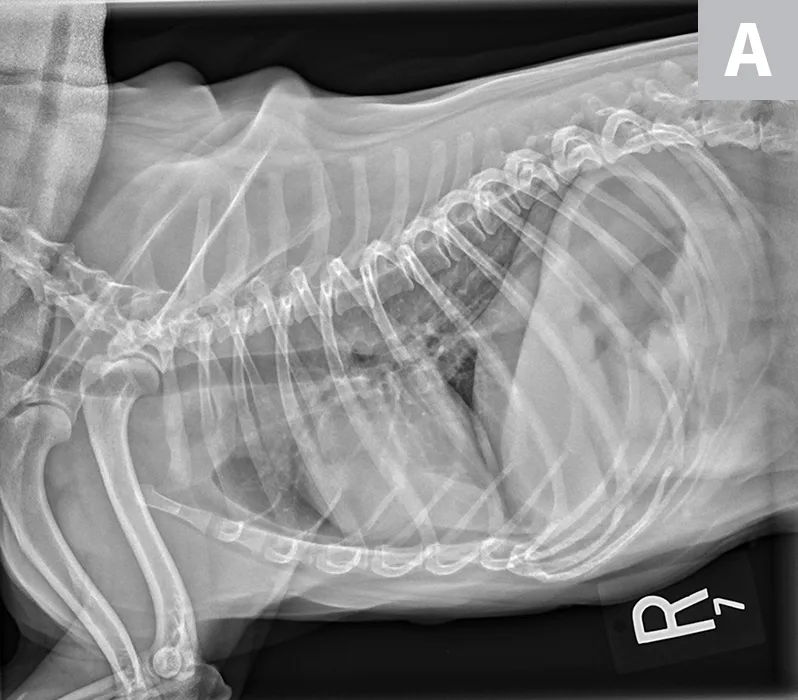

Lateral radiographs of a 2-year-old cat (A) and a 9-year-old cat with increased sternal contact of the cardiac silhouette (B).

Thoracic radiographs are generally difficult to assess in cats due to age-associated variability. The cardiac silhouette develops increased sternal contact as cats age (Figure 1), with the aorta creating a notch or right-angled appearance that can falsely suggest left atrial enlargement on ventrodorsal projection. The aortic arch may have a rounded appearance on the ventrodorsal projection that can be mistaken for a pulmonary nodule in the left cranial lung lobe (Figure 2).1